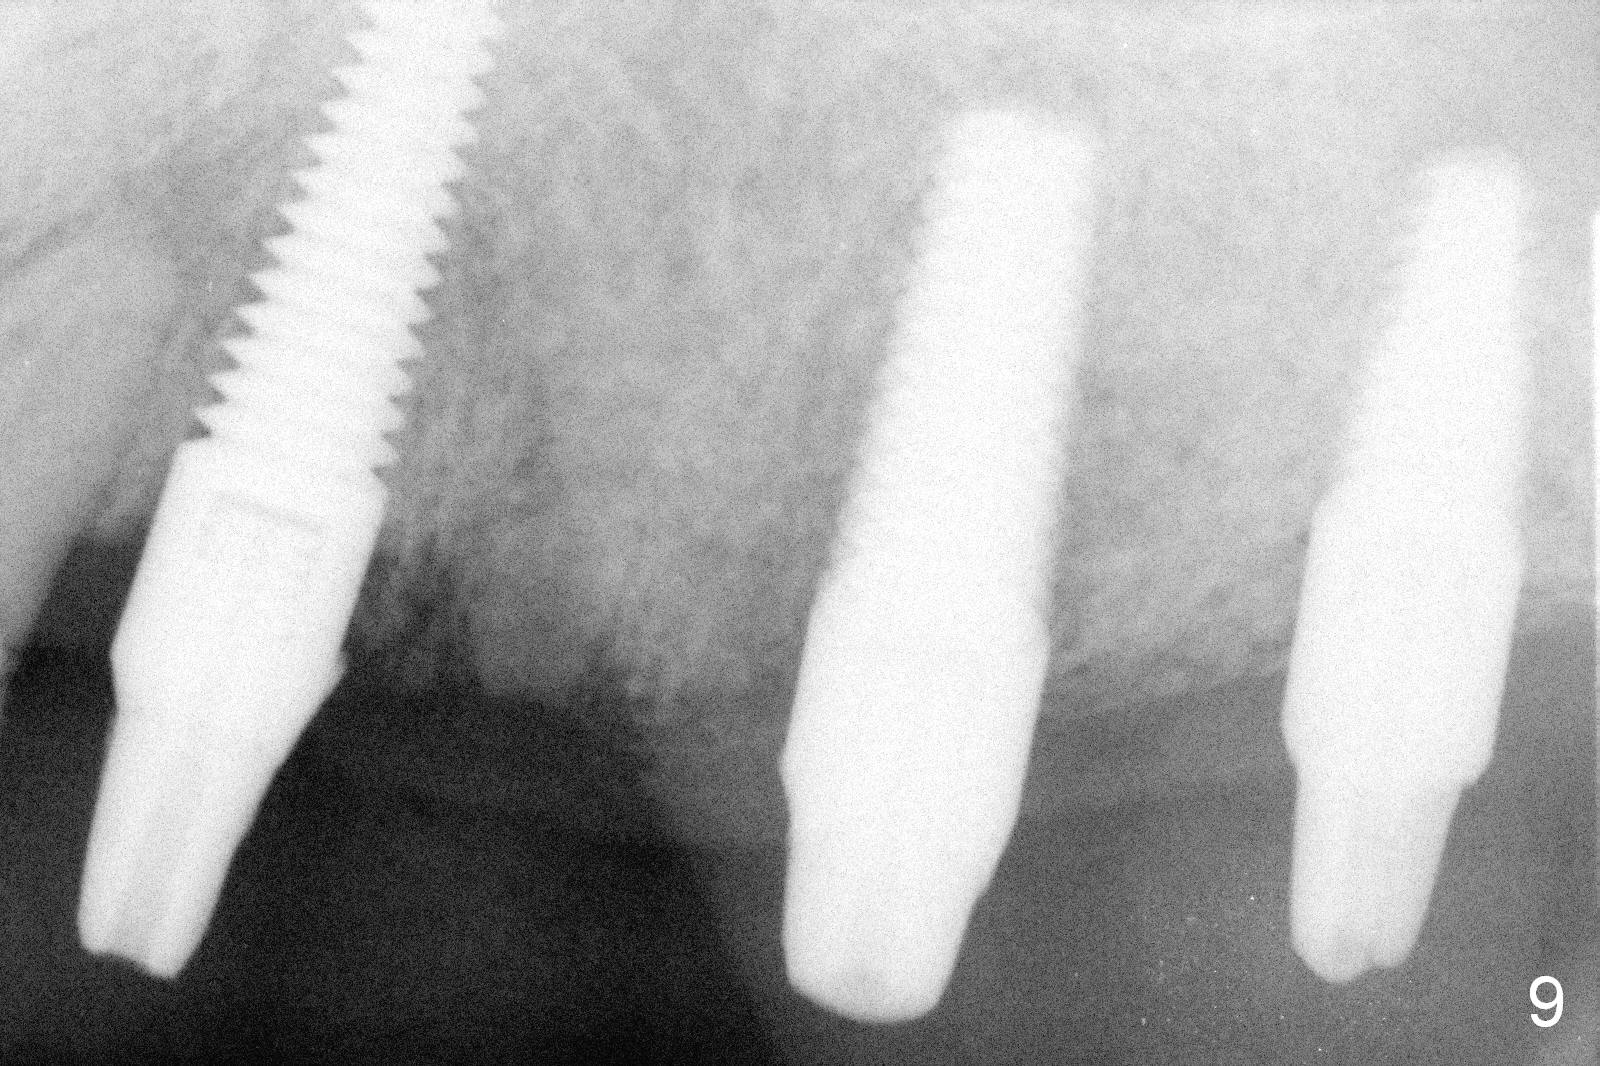

The patient returns for definitive restoration 3.5 months postop (Fig.9). A full arch custom tray is used to take final impression. Bite registration is taken. The opposing arch is available in the lab shelf. Make a 3-unit bridge between #11 and 14 (one premolar) and a single-unit at #15. Technician: please mount properly and check occlusion repeatedly.